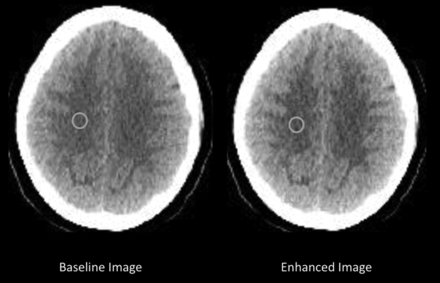

All baseline and enhanced images were converted into DICOM format using the JPEG to DICOM plugin for Osirix Lite (Pixmeo, Bernex, Switzerland) for quantitative analysis. Means (SI) and SDs of the gray matter (gm) and the white matter (wm) intensities were measured from equivalent ROIs in the baseline and enhanced images (Fig 2). These measurements were then used to calculate gray matter conspicuity and the CNR between gray and white matter using the following formulae:

For images obtained at the ganglionic level, GM was sampled in the putamen and white matter in the frontal lobe. For the supraganglionic images, GM was sampled along the cerebral convexity and the white matter within the centrum semiovale.

Axial head CT image across the centrum semiovale before (baseline image) and after (enhanced image) processing with CIE, with equivalent ROIs used to measure gray and white matter intensities. These measurements were used to calculate the conspicuity of gray matter and CNR between gray and white matter.